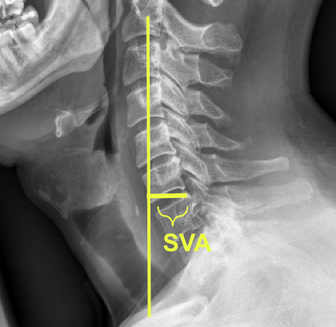

Image Type Cervical Spine X-Ray CT Scan MRI Scan Atlantodental Interval (ADI) Basion-Axial Interval Basion-Dens Interval (BDI) C2 Tilt C2–C7 Coronal Cobb Angle Cervical C2-7 lordosis C2-C7 Translation Chamberlain’s Line / McGregor’s Line Flexion-Extension George’s Line (Posterior Cervical Line) K-Line Interpedicular Distance (IPD) Occiput-C2 Angle Occipital Condyle–C1 Interval (CCI) Posterior Atlantodental Interval (PADI) Power’s ratio Sagittal Canal Diameter Sagittal Vertical Axis (SVA) Spinolaminar line Swischuk Line T1 Slope Torg/Pavlov Canal-to-Body Ratio